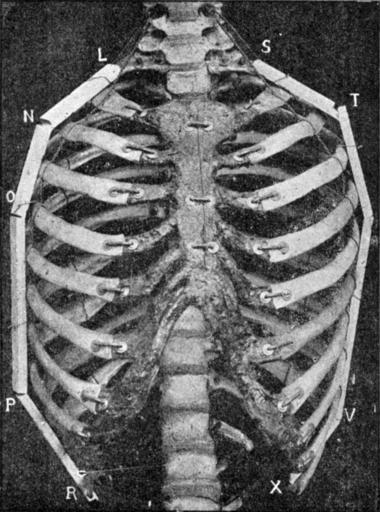

| Keywords: Corset1908 038Fig17.png Fig 17 ” Seconde dĂ©monstration photographique de l'aspect doliforme de thorax page 38 1908 Doctcur O'FOLLOWELL PD Image Corset1908_038 png PD-old Le Corset 1908 Bones | ||||